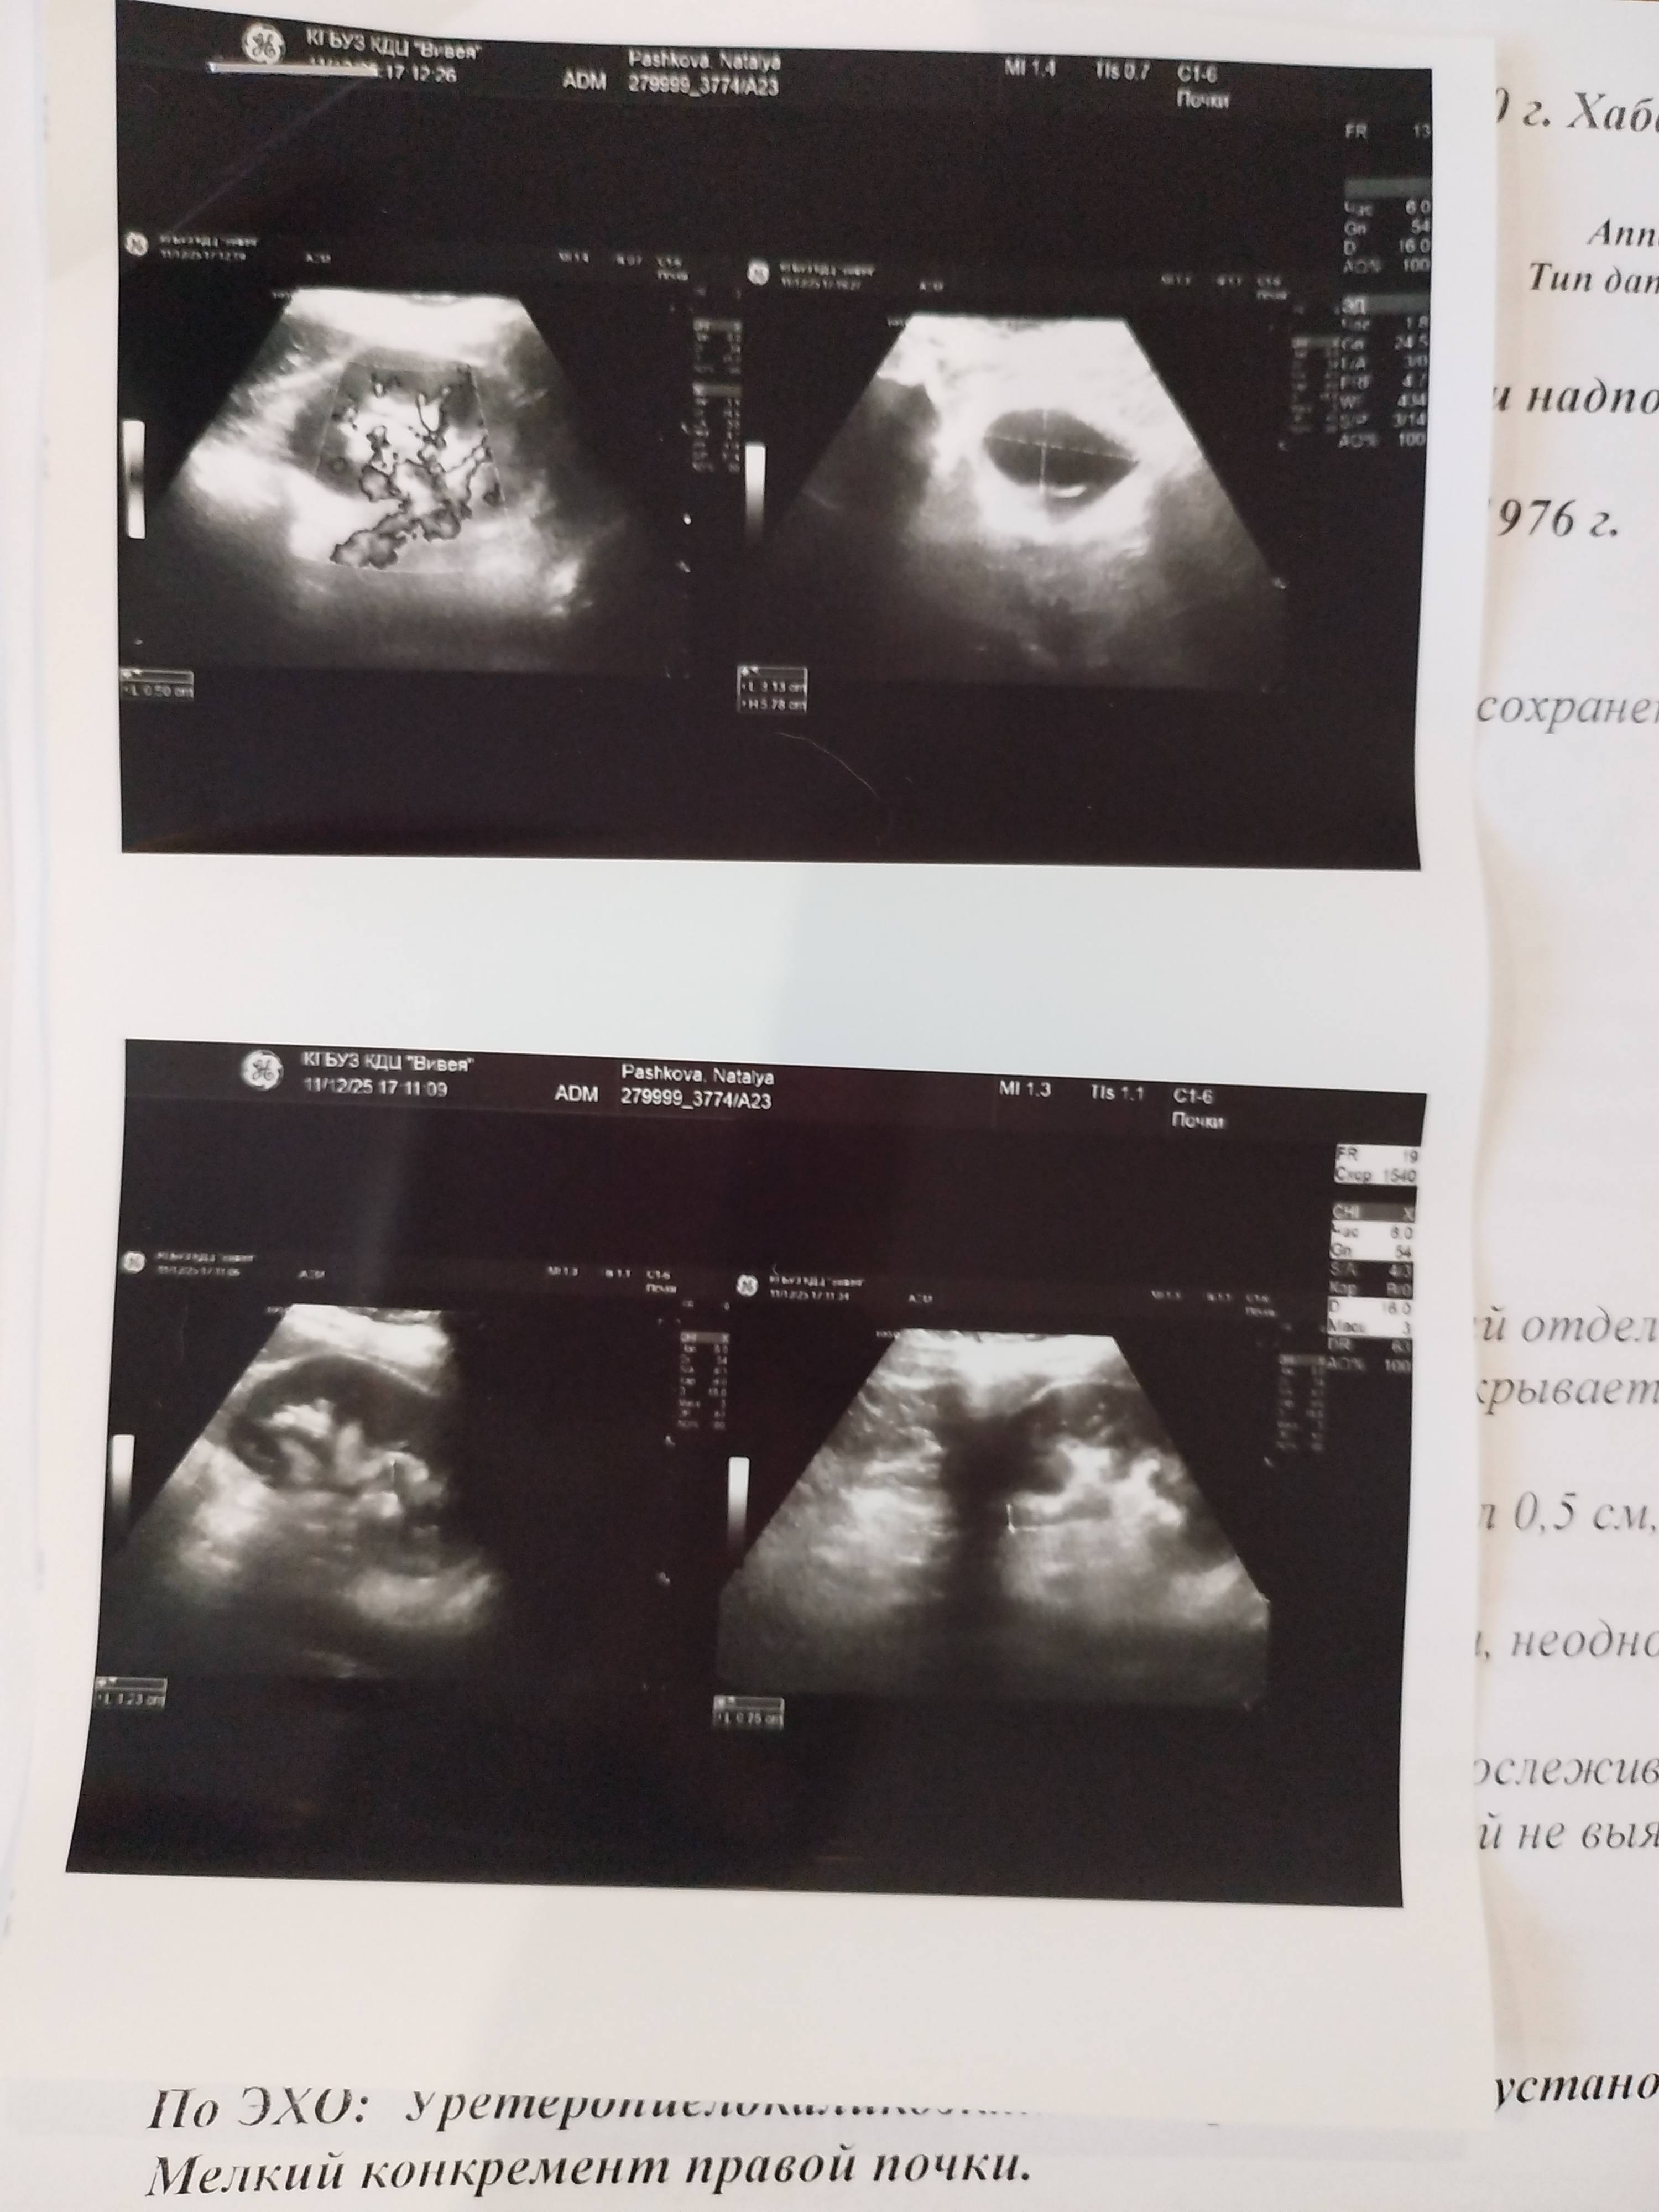

Здравствуйте уважаемые участники сайта! Хочу рассказать о своей проблеме. Я оказалась в тяжёлой жизненной ситуации. Недавно переехала в другой город. Сняла квартиру, устроилась на работу. Внезапная смерть мамы , попадение в больницу папы подорвали моё здоровье. Я попала в больницу с диагнозом гнойный пиелонефрит правой почки. Мне сделали операцию по установке стенда. Пробыла в больнице 8 дней. После выписки пришлось уволиться с работы, я продавец кассир. Работала на кулинарии (салаты, горячее, выпечка). Сейчас сами понимаете самый сезон для торговли (предновогодняя суета). Неделю после выписки провела дома, после прикрепилась к поликлинике и попала к урологу на приём. Меня после выписки дней через 5 стали беспокоить частые мочеиспускание и неприятные ощущения внизу живота. Даже 1 день была моча с кровью. Врач мне объяснил что это реакция организма на инородное тело (стенд). В общем так получилось что мне нельзя никакой физической нагрузки, активности. Хотела выйти на подработку, но не могу долго ходить из-за дискомфорта внизу. У меня камень до 1см. сейчас находится в мочеточнике. Операция плановая назначена на 14 января. Стенд создает мне дискомфорт и я не могу из-за этого работать. После операции сразу же выйду на любую работу. Но сейчас мне нужно оплачивать съёмную квартиру и покупать необходимое еду. Прошу у вас финансовой поддержки, по мере возможности. Буду вам очень благодарна. Если понадобится скинуть фотографии узи и документов, скину. Вашу поддержку я жду на карту дочери, так как у меня арестованы счёт и карта из-за долгов по кредитам. Для перевода денежных средств номер карты 5469700015562885 (Анастасия Николаевна, сбербанк) Спасибо вам большое за любую вашу помощь. С благодарностью , Наталья.